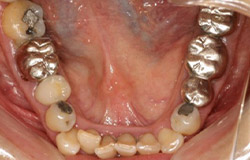

インプラントで噛み合わせの再構成を伴った症例。

治療後のメンテナンスを行わないと

周囲炎になるリスクあり。